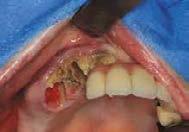

Se presenta una paciente de 29 años con el motivo de consulta “quiero arreglarme los dientes” en los

estudios de inicio se observa en la radiografía lateral de cráneo (Figura 1) clase II esquelética y crecimiento vertical. En los estudios de inicio extraorales en las fotografías de frente y perfil (Figura 2) no muestra exposición dental al momento de sonreír, un perfil convexo y el tercio inferior aumentado respecto al tercio superior y medio de la cara.

Figura 1. Lateral cráneo.